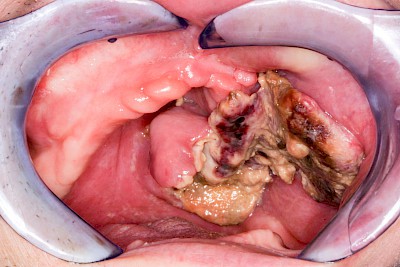

Einschmelzung & Geschwür

Das Risiko für Krebs der Mundhöhlen-Schleimhäute ist bei Menschen, die jahrelang übermäßig viel (Abusus) geraucht und erst recht lange übermäßig viel Alkohol getrunken haben, stark erhöht. Die Schleimhäute sehen dann aus wie "wildes Fleisch" – entweder mit blumenkohlartigen Auftreibungen oder aber es zeigen sich großflächige ungleichmäßig geformte Defekte und Einschmelzungen. Man spricht dann auch von einem Geschwür (Ulcus).

Entsteht der Krebs eher in tieferliegenden Schichten (z. B. im Bereich der Speicheldrüsen), sind die Auffälligkeiten nicht so deutlich. Hier fallen eher Seitenunterschiede links und rechts im Bereich der Mundhöhle auf. Auch plötzlich auftretendes und wiederholtes Nasenbluten, Einschränkungen der Atmung durch die Nase können Anzeichen für einen Tumor im Bereich der Nasen- oder Kieferhöhle sein.

Selten können auch Fibrome oder Druckstellen bei Zahnprothesen, wenn diese nicht erkannt und behandelt werden, in "wildes Fleisch" übergehen und hin zu bösartigen Tumoren entarten.

Bei allen diesen Auffälligkeiten ist eine sofortige (zahn-)ärztliche Abklärung zu veranlassen.